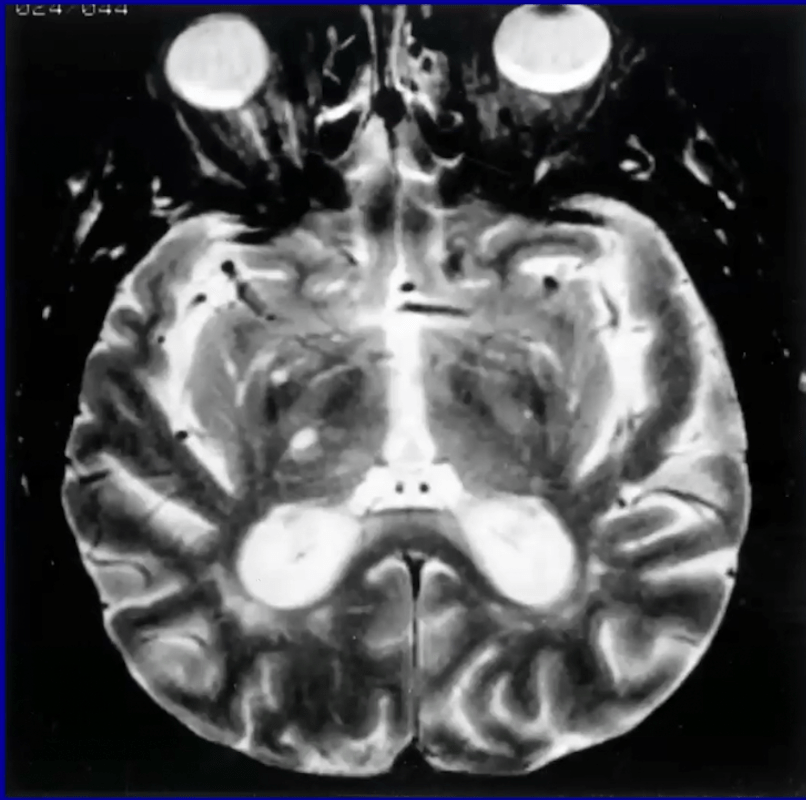

Occlusion of which vessel(s) cause this stroke?

Artery of Percheron